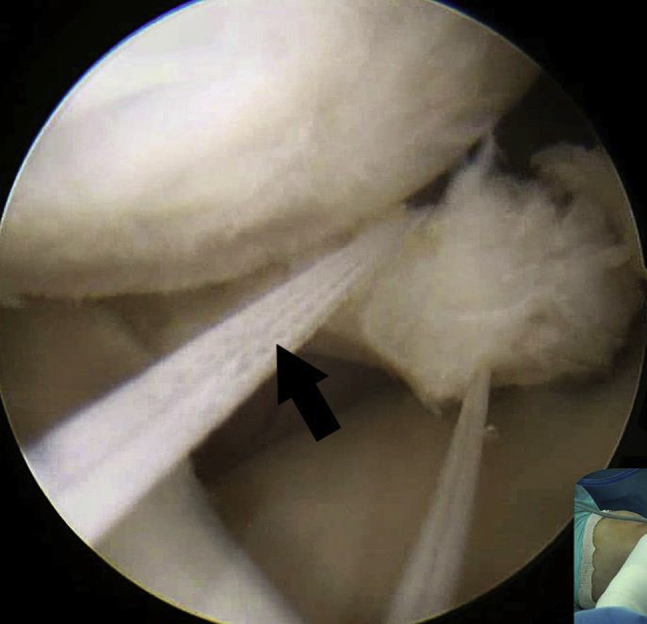

Fig 1.

Viewing from the anterolateral portal, a 6-mm-wide tibial tunnel is created using FlipCutter (Arthrex) at the anatomic medial meniscus posterior root insertion (black arrow) on the left knee.

Viewing from the anterolateral portal, the torn medial meniscus posterior root is debrided to refine the edge, and landmarks relevant to the insertion of the posterior root of the medial meniscus, including the posterior cruciate ligament insertion, medial tibial spine, and articular margin of the tibial plateau, are identified. The anterior cruciate ligament reconstruction tibial guide (Linvatec) tip is placed at the anatomic posterior root insertion via the anteromedial portal; a guide pin is then drilled through the guide from the medial side of the tibial tuberosity. After confirming that the tibial tunnel is suitable and the guide pin is well positioned, the guide pin is pulled back through. Next, a 6-mm FlipCutter (Arthrex, Naples, FL) is introduced into the anatomic root insertion from the exit of the tibial tunnel following the previously drilled tibial tunnel and then it is retro-drilled to the exit of the tibial tunnel, making a 6-mm-wide tibial tunnel (Fig 1).